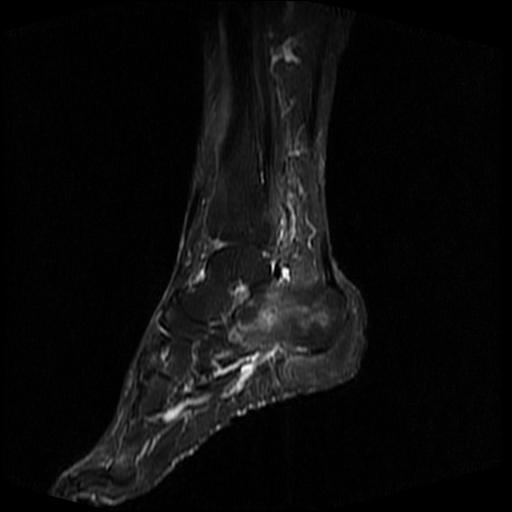

女性,70岁,右侧跟骨疼痛2个月,负重时加剧,不负重时不疼。

胫骨下段,跟骨、距骨可见斑片状异常信号区;考虑:转移瘤

跟骨长t1长t2信号异常,边缘模糊(肿瘤一般边界清楚,故肿瘤不考虑),压脂像呈高信号--骨髓水肿(炎症?)。